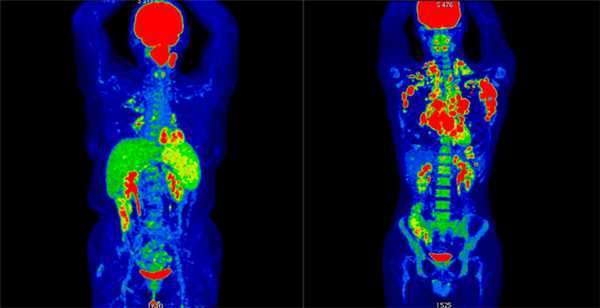

Результаты ПЭТ/КТ-исследования. Слева: неходжкинская лимфома (поражение левой небной миндалины и селезенки, поражение лимфоузлов выше диафрагмы. Справа: ходжкинская лимфома (поражение лимфоузлов по обе стороны от диафрагмы, с тенденцией к слиянию в массивные конгломераты, наиболее крупные в подмышечной области слева и в лимфоузлах средостения справа. III стадия)